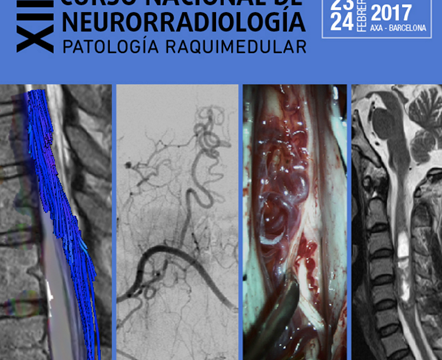

Curso Nacional de Neurorradiología

23-24 de febrero de 2017 Barcelona Programa Cartel Presentaciones Localización L’illa Diagonal, Avinguda Diagonal, 547, 08029 Barcelona